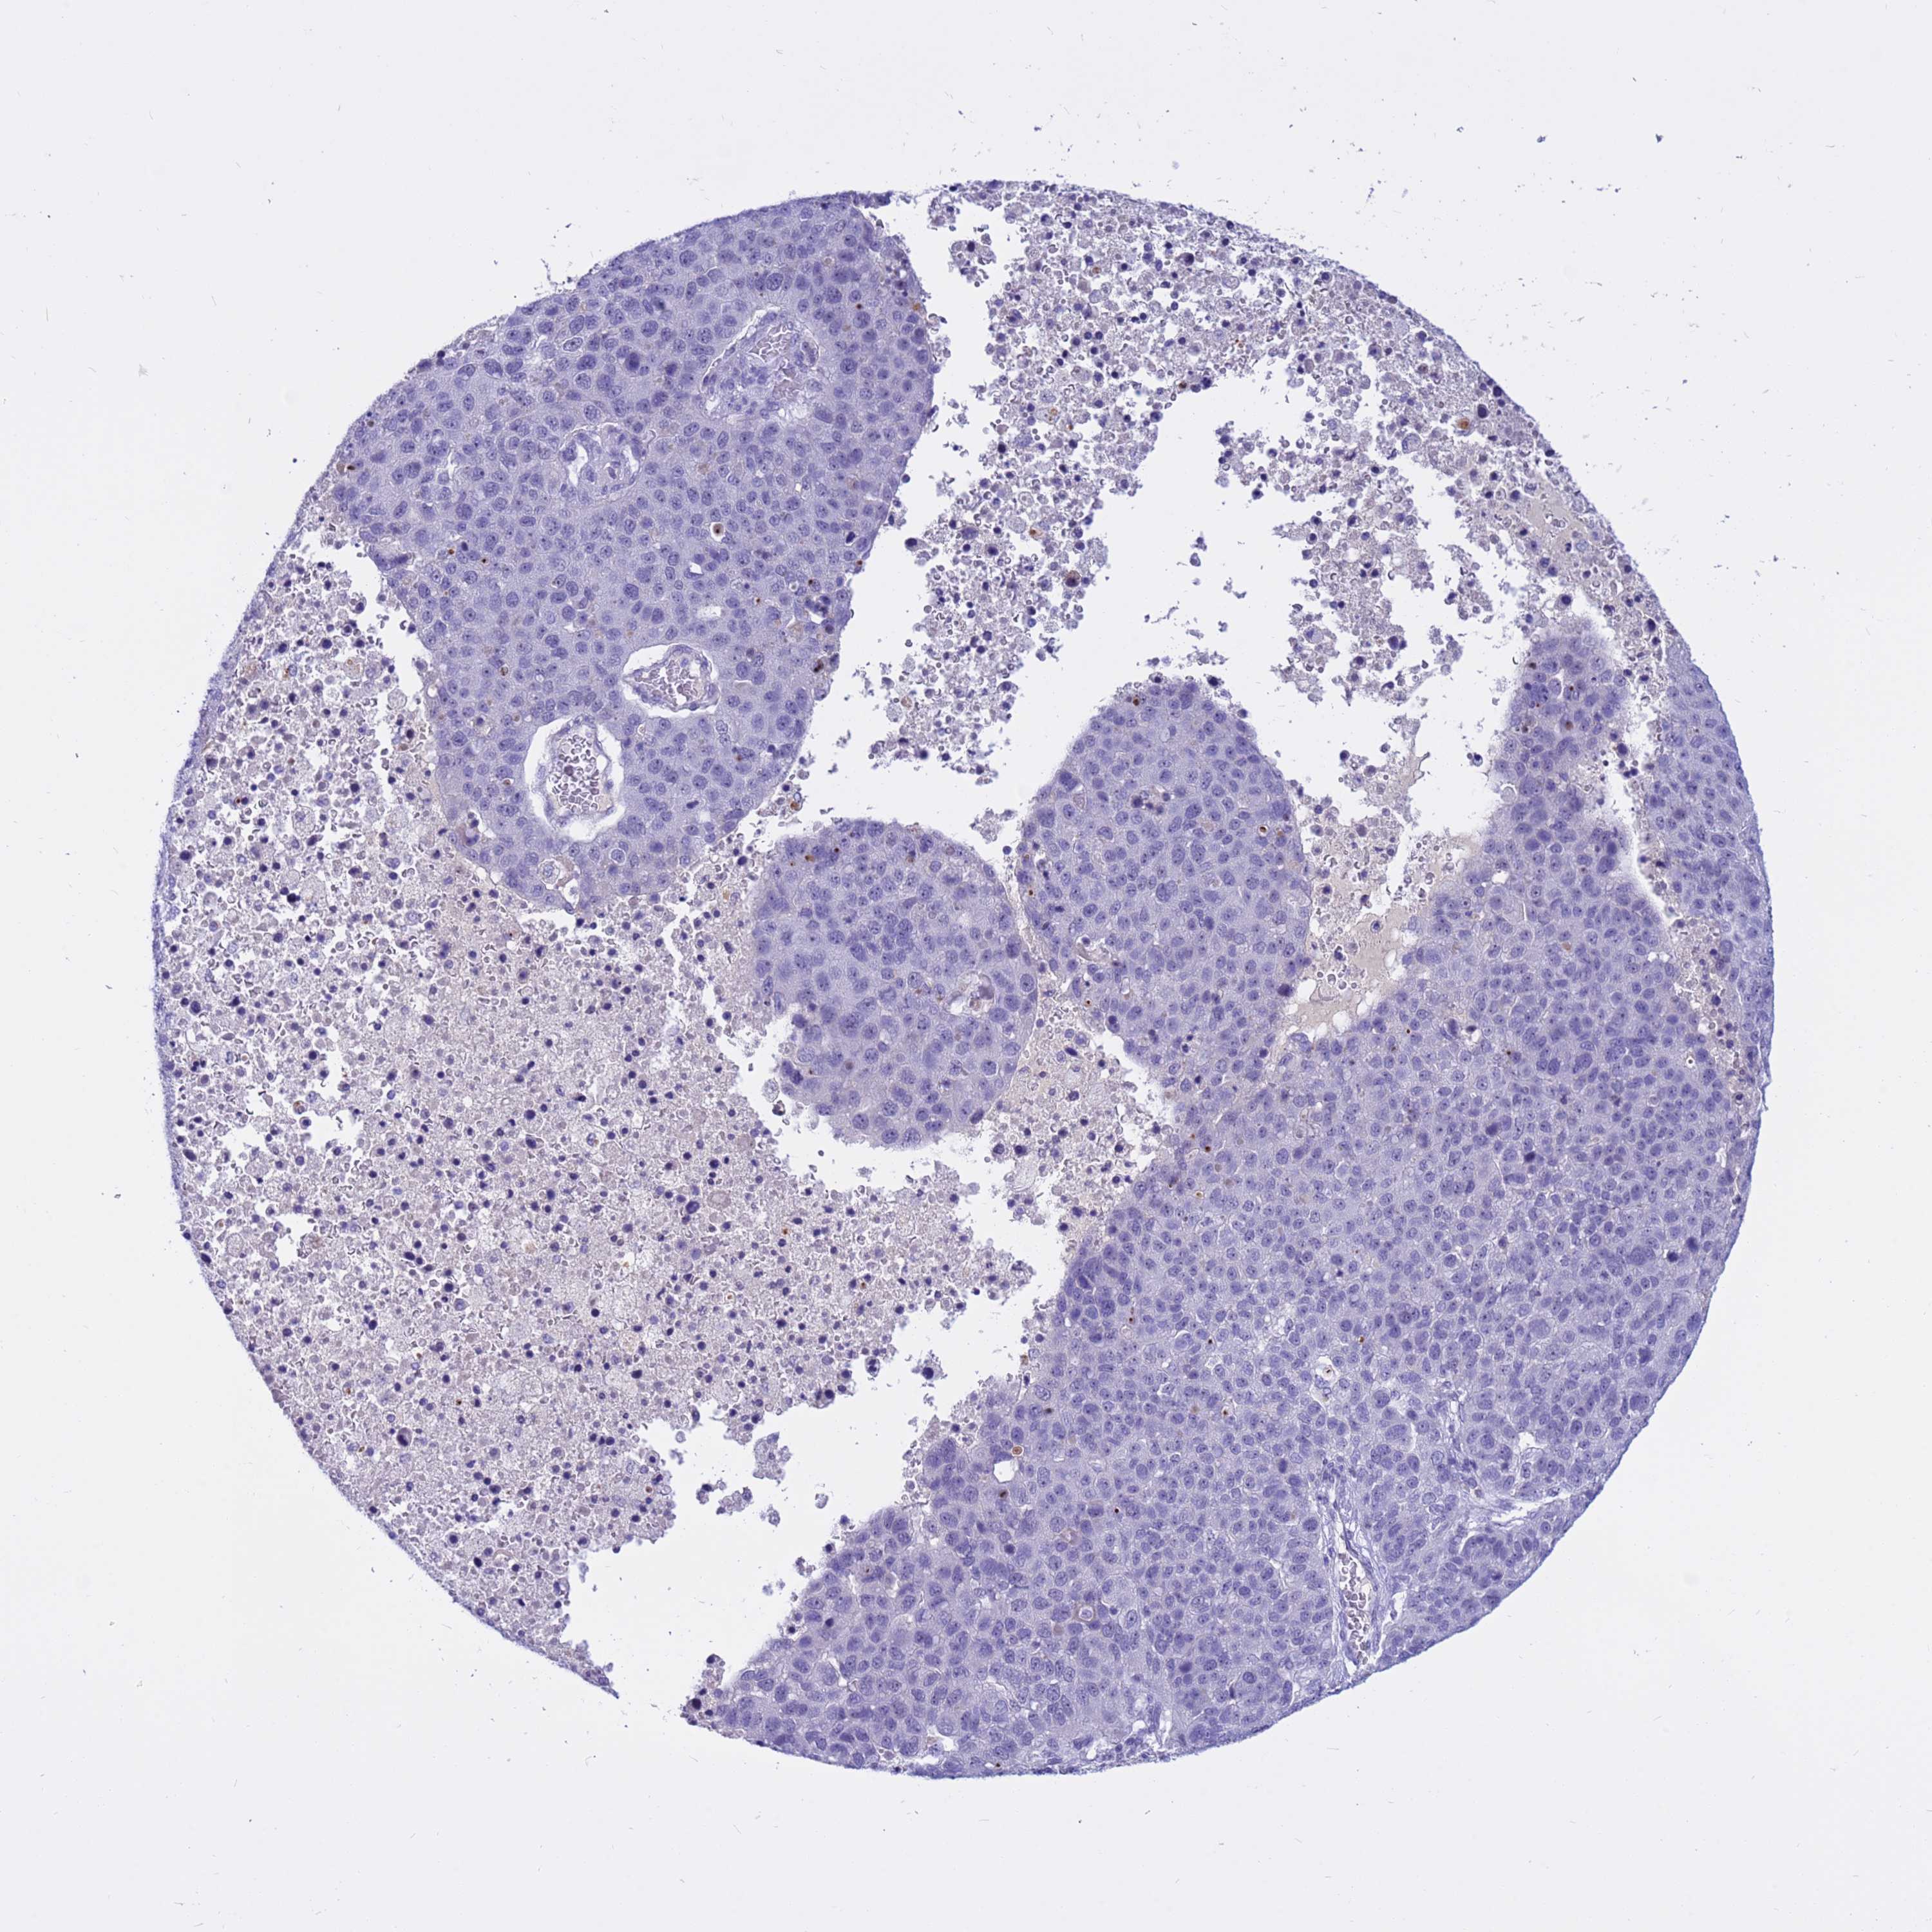

PANCREATIC CANCER - Protein expressioni

A mouse-over function shows sample information and annotation data. Click on an image to view it in a full screen mode. Samples can be filtered based on level of antibody staining by selecting one or several of the following categories: high, medium, low and not detected. The assay and annotation is described here.

Note that samples used for immunohistochemistry by the Human Protein Atlas do not correspond to samples in the TCGA dataset.

Antibody stainingi

Antibody staining in the annotated cell types in the current human tissue is reported as not detected, low, medium, or high, based on conventional immunohistochemistry profiling in selected tissues. This score is based on the combination of the staining intensity and fraction of stained cells.

Each image is clickable and will lead to virtual microscopy that enables deeper exploration of all samples and also displays staining intensity scores, fraction scores and subcellular localization as well as patient and tissue information for each sample.

Antibody HPA045016

Staining

High

Medium

Low

Not detected

Intensity

Strong

Moderate

Weak

Negative

Quantity

>75%

75%-25%

<25%

None

Location

Nuclear

Cytoplasmic/membranous

Cytoplasmic/membranous,nuclear

Adenocarcinoma, NOS